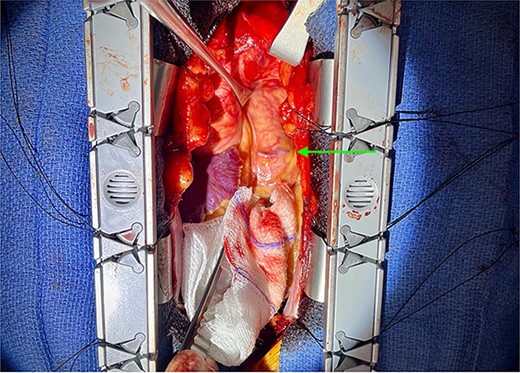

A median sternotomy was performed, and the LIMA was harvested. The CPF was identified (Fig. 3) and ligated using three figure-of-eight sutures (Fig. 4), with additional clips applied to control flow through a secondary branch. The fistula was ligated at multiple location to decrease the chances of recanalization. Cardiopulmonary bypass (CPB) was initiated and LIMA-LAD anastomosis was performed. CPB was successfully weaned without complications. The patient was transferred to the cardiovascular intensive care unit in stable condition.

Ligation of coronary to pulmonary artery fistula with figure-of-eight sutures.